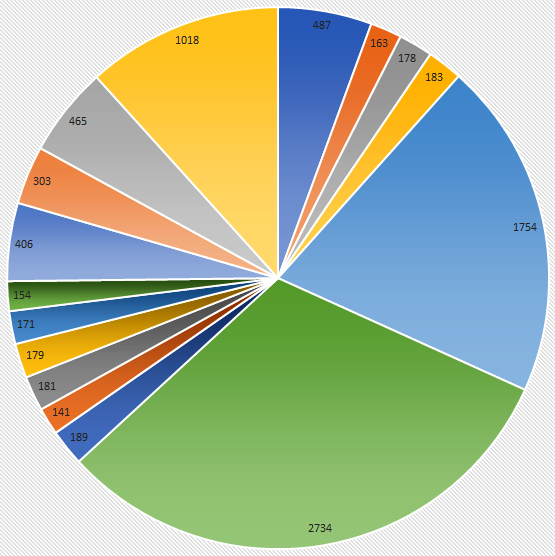

Some Common Operative Procedures